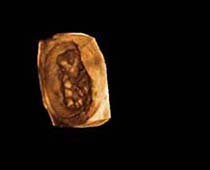

- صور لوجه الجنين في داخل الرحم

- صور جانبية لرأس الجنين

- صور للجنين في المراحل الأولى من الحمل

صور لأجنة ثلاثية الأبعاد بجهاز الموجات فوق صوتية | الدكتور نجيب ليوس